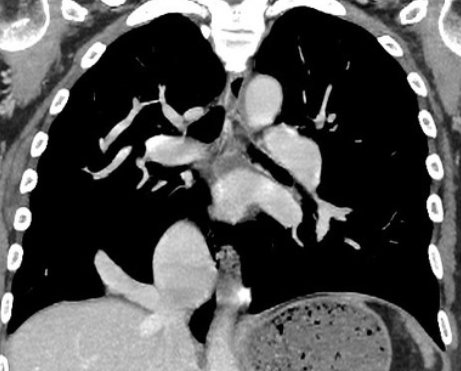

- Bande de parenchyme pulmonaire entre les deux lobes inférieurs